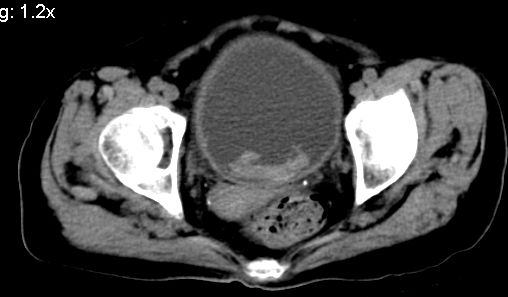

膀胱充盈可,壁光滑厚薄尚均匀,其内下方可见不规则的致密影,建议做膀胱镜检查

膀胱癌突破浆膜可能性大

考虑膀胱癌可能性大伴双侧输尿管下端扩张.

膀胱后壁见不规则致密影,我们遇到这样的病人都再做一次俯卧位扫描;排出膀胱内凝血块。

1.膀胱后壁见不规则致密影,占位?膀胱内凝血块?建议俯卧位扫描、膀胱镜检查.

2.双侧输尿管下段扩张.

膀胱三角区不规整软组织改变,双侧输尿管扩张,所以占位性病变肯定首先考虑,建议改变体位扫描除外游离血块影,但老年人出血原因一定要查明。

1.膀胱后壁见不规则致密影,随体位改变,为膀胱内凝血块;

2.双侧输尿管下段扩张.输屎管结石可能大。建议作进一步检查。